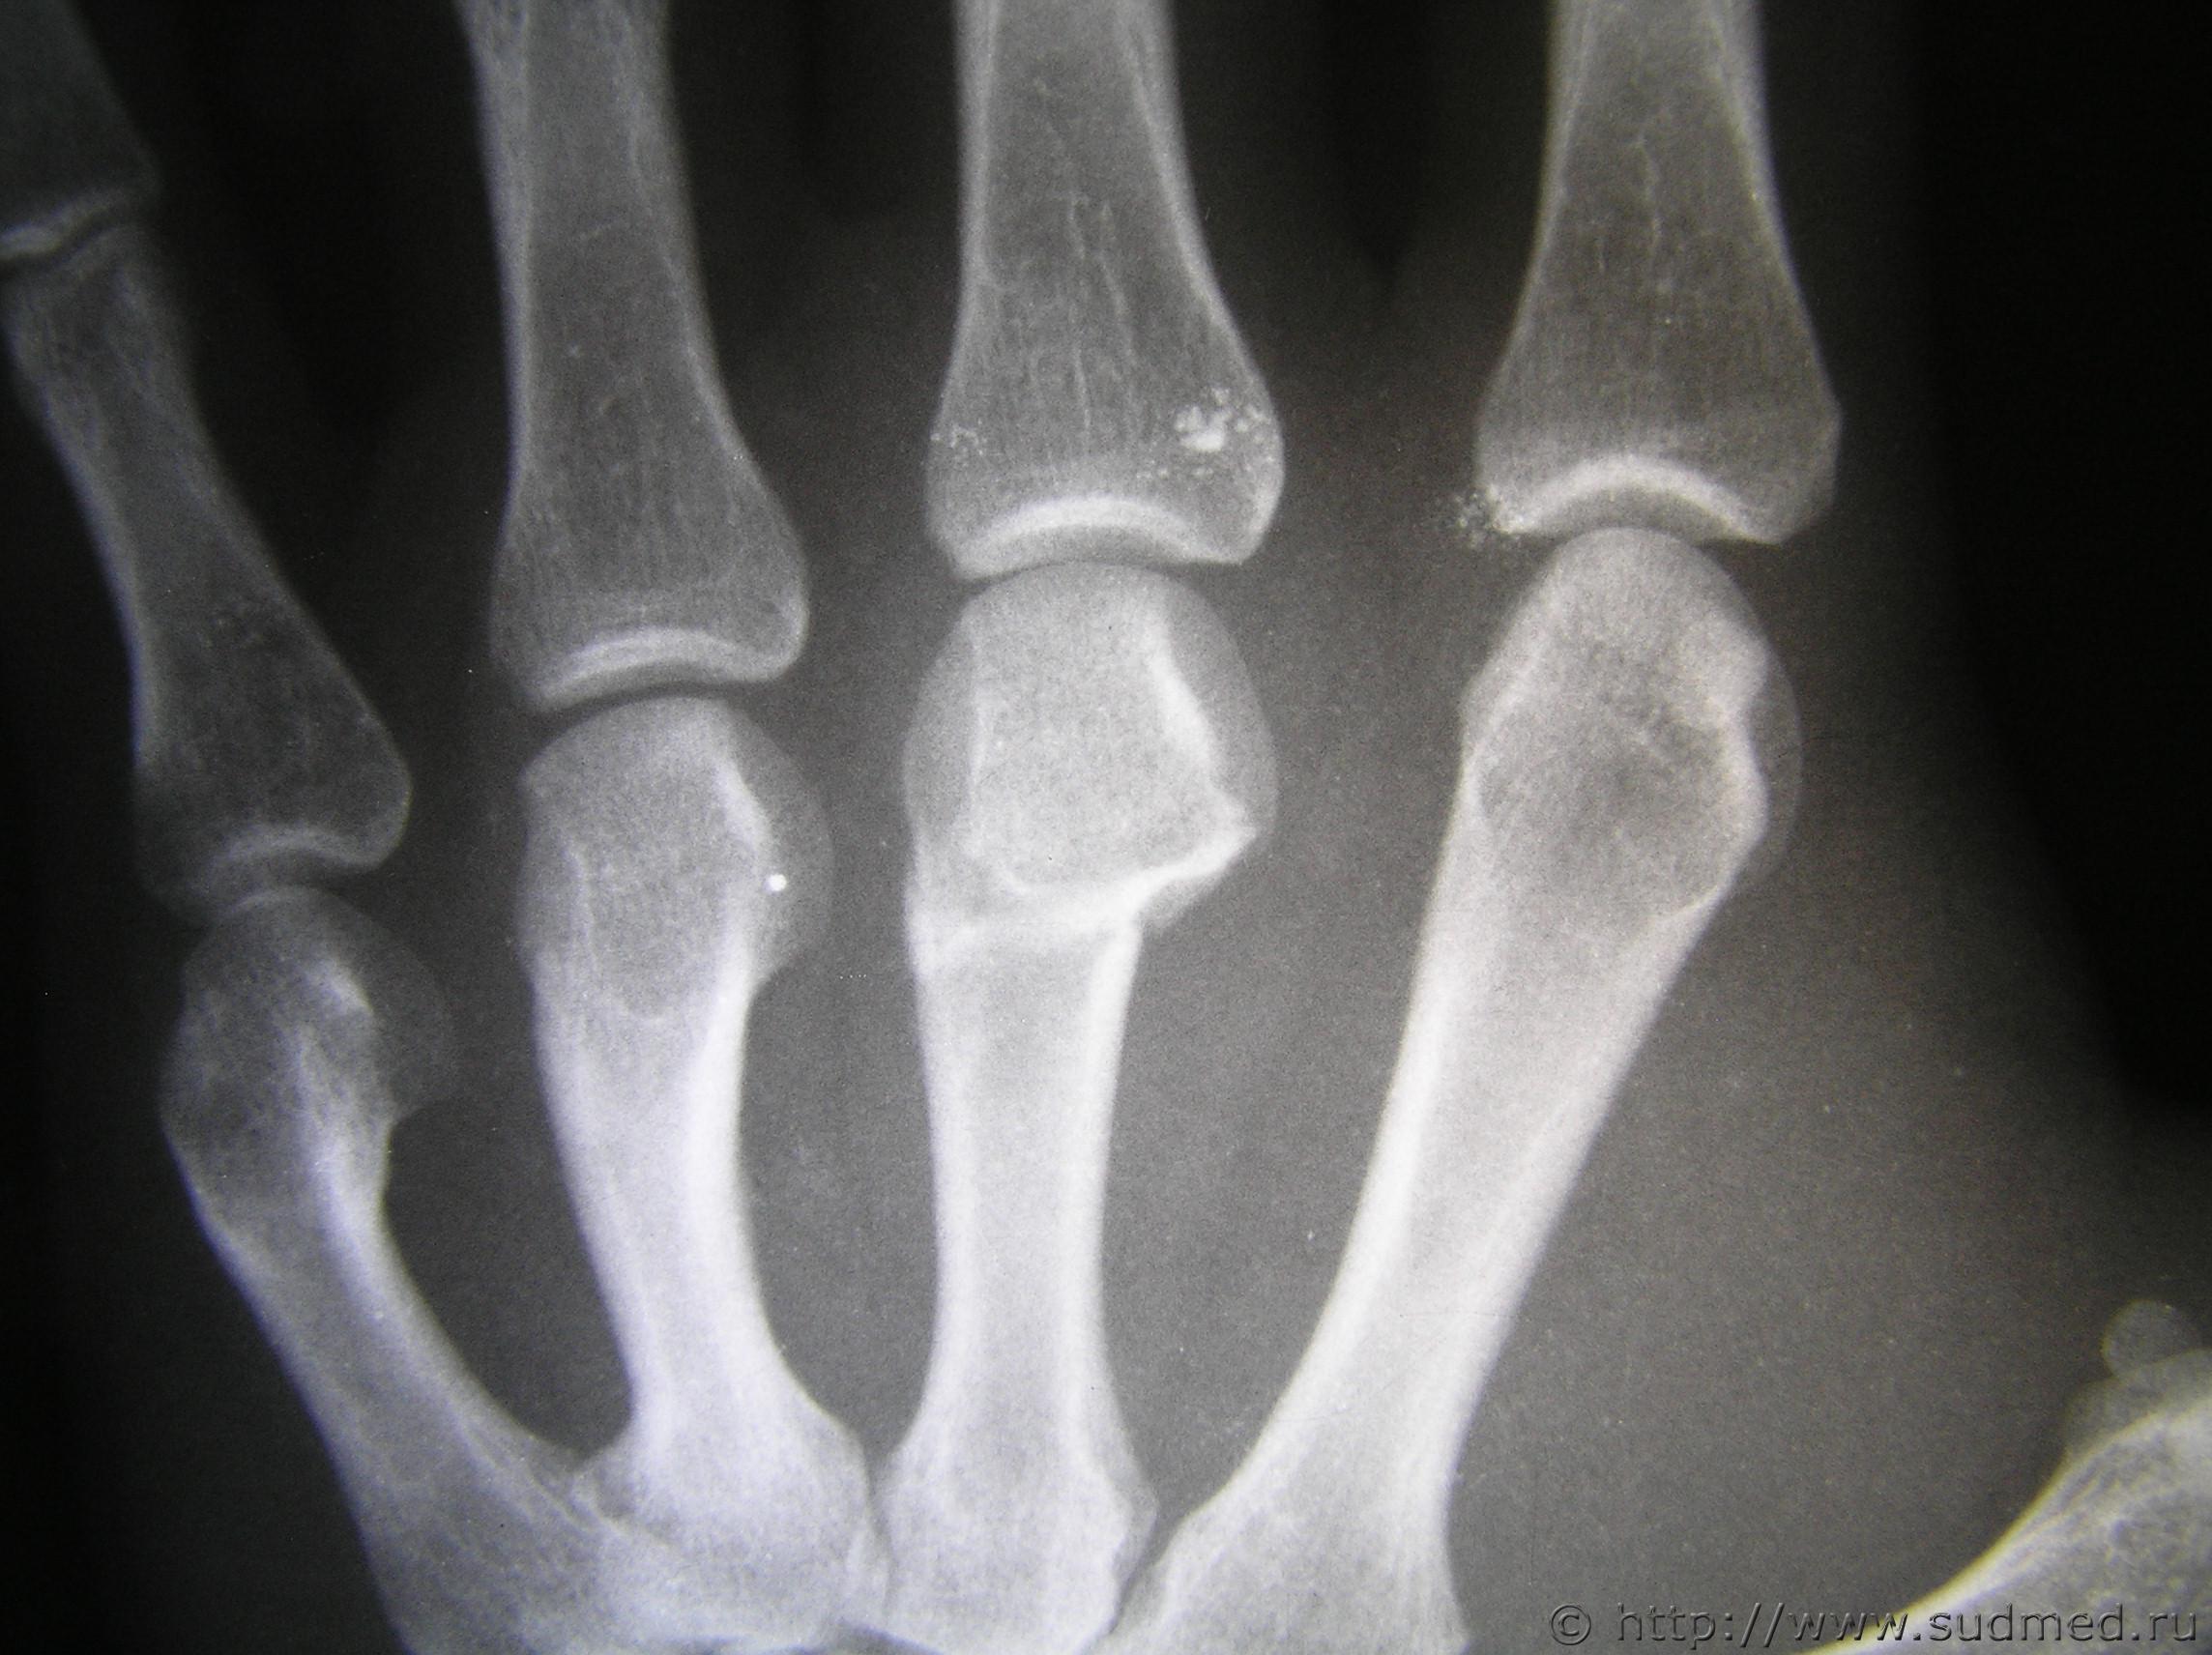

вот рентген. может есть на форуме специалисты которые смогут помочь smile.gif

рентгенография правой кисти

Удар кулаком.

Полностью согласен. удар с упором на пястно-фаланговые суставы

Согласен- нагрузка по оси кости.

боксер не боксер, а наносить удар сломаннной рукой вряд ли кто стал, да еще и при наличии другой, здоровой руки) а тут еще и рентген - осевая нагрузка, так что согласен с остальными - удар рукой

Удар кулаком 100%.Доказано, что при нанесении прямого удара основная нагрузка приходится на II—III пястные кости.+нагрузка по оси.